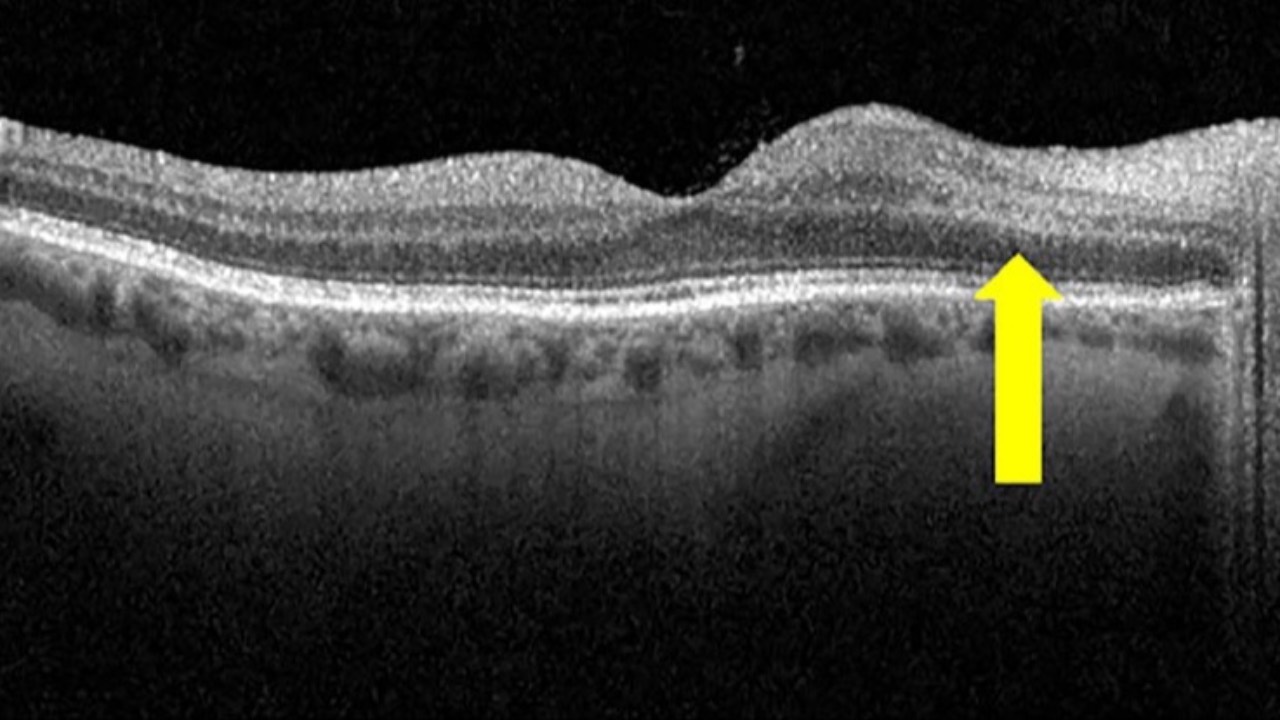

Paracentral acute middle maculopathy (PAMM) and retinal fluid may serve as high-yield biomarkers in distinguishing between arteritic anterior ischemic optic neuropathy (AAION) and non-arteritic anterior ischemic optic neuropathy (NAION). It appears the presence of...